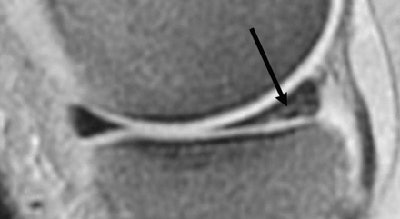

![]() |

| Conventional spin-echo versus fast spin-echo imaging for detection of meniscal tear in 50-year-old woman. Sagittal fast spin-echo proton density-weighted MR image (3,000/17) with fat suppression obtained through medial meniscus does not show meniscal tear. Garyun BB, Major NM, Helms CA, "Comparison of Fast Spin-Echo Versus Conventional Spin-Echo MRI for Evaluating Meniscal Tears" (AJR 2005; 184:1740-1743). |